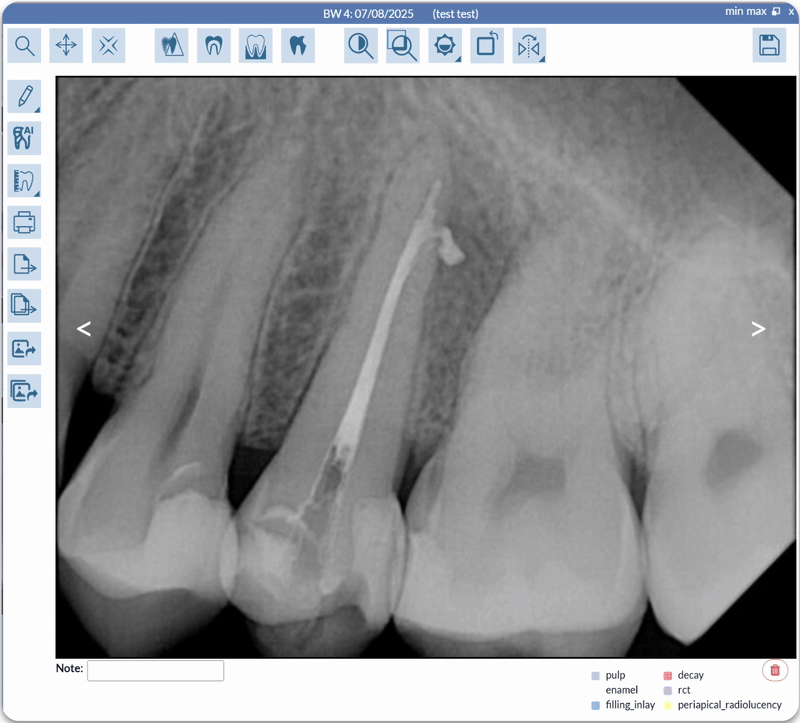

One of Oryx’s AI partners specializes in real-time image analysis that identifies and quantifies conditions such as decay, bone loss, and calculus directly on dental X-rays. Its chairside annotations transform static images into interactive learning tools — helping patients grasp the “why” behind every recommendation.

Because this technology meets rigorous FDA standards, many insurance carriers recognize its annotated imagery as authoritative, often leading to smoother claim approvals and fewer denials. Practices using it have reported measurable gains in efficiency and treatment acceptance, thanks to clearer communication and consistent documentation.

Another of Oryx’s imaging AI integrations has earned regulatory clearance across multiple international markets, making it the first and only solution of its kind to operate globally at the chairside level. Its algorithms detect a wide range of conditions on bitewing, periapical, and panoramic images — assisting dentists in identifying pathologies earlier and standardizing diagnostic quality across the practice.